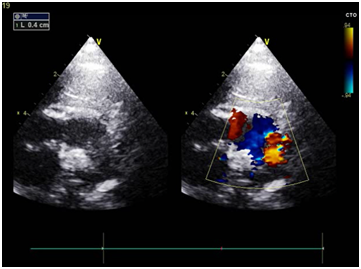

Echocardiography showed: PDA 4 mm with left to right shunt (Figure 2).

Figure 2 Short axis view Echocardiogram showed the size of the PDA.